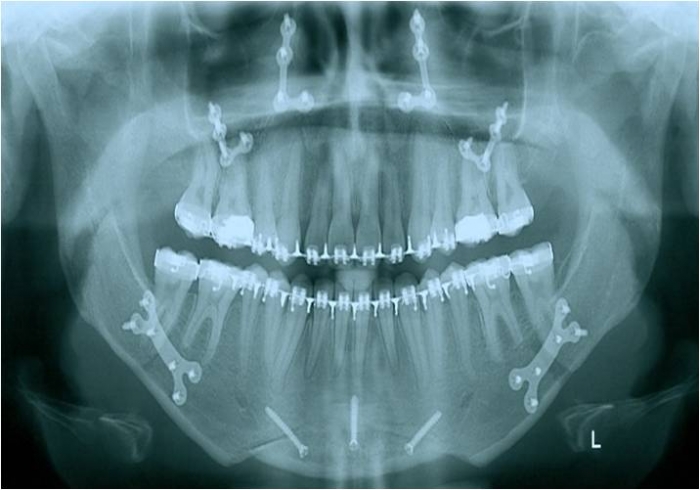

Raio x inicial

Raio x após a cirurgia